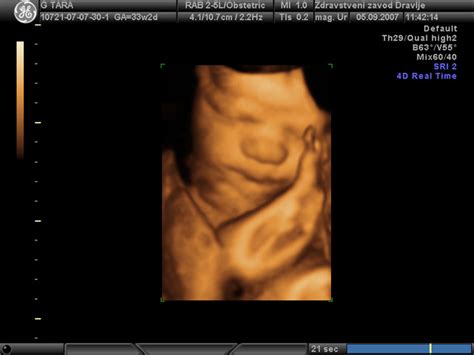

Ultrazvok je primarna diagnostična metoda za ugotavljanje ventrikulomegalije med nosečnostjo. Rutinski UZ pregledi, kot je morfologija ploda, omogočajo oceno velikosti možganskih prekatov. Če se ugotovi odstopanje, se lahko priporočijo dodatni, natančnejši UZ pregledi, pogosto v specializiranih ustanovah ali terciarnih ambulantah, ki imajo naprednejšo opremo in izkušene strokovnjake.